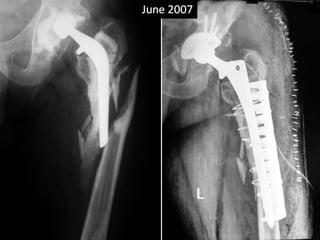

June 2012

Surgery

• Shaft pieces were approximated with cerclage

wires over a solution stem.

• A Mennen plate was used to hold the pieces

together and further enforcement was done

by few screws and wires.

• Post op sciatic palsy.

• Immobilization continued for 3 months